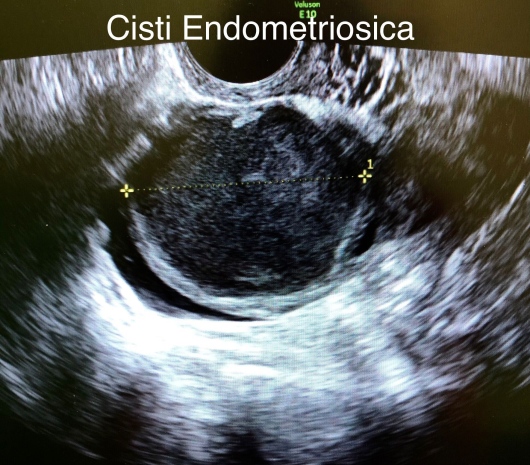

Ho lavorato infatti presso il Policlinico Gemelli di Roma al centro di Ecografia Class Ultrasound, dove ho eseguito in prima persona ecografie ginecologiche di II livello, sia in ambito oncologico (diagnosi del tumore dell’ovaio e dell’utero) sia per la diagnosi di Endometriosi ed Endometriosi Profonda.

• Endometriosi